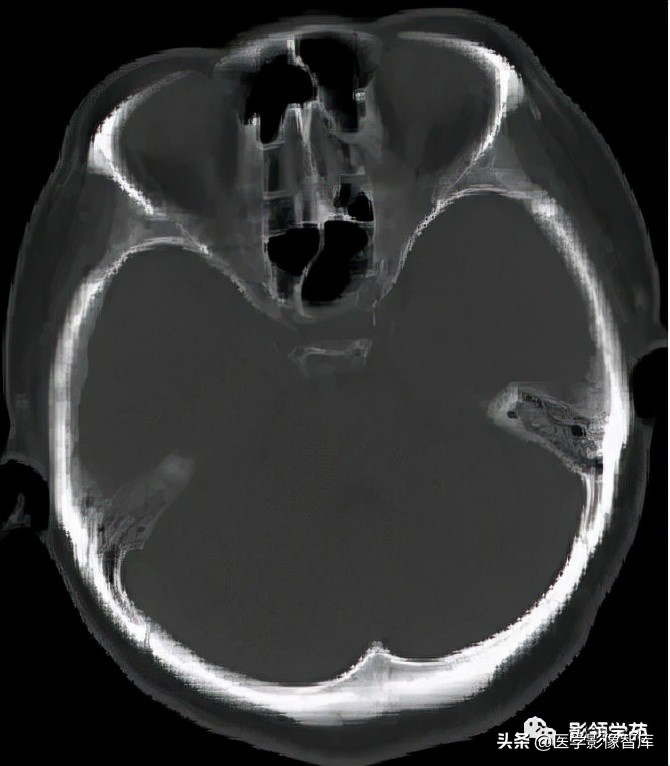

女 61岁 反复头晕3年余

鞍上可见一类圆形均匀稍高密度灶,CT值约47HU,

边界清楚,其内见一小点片状钙化灶;继发鞍上池受压伴变性。

鞍区占位肿块,呈等T1等T2信号,信号均匀,边界清楚。

病灶呈均匀、显著强化(馒头样),以宽基底与前颅窝底相连,

冠状位和矢状位见脑(硬)膜尾征;

肿块突入鞍上池,向上推压视交叉,后缘紧邻垂体柄,与双侧颈内动脉相邻。

(脑膜尾征:增强扫描,肿块邻近的增厚硬脑膜呈窄带状强化,随着远离肿瘤

而逐渐变细。)

颅内动脉走形自然,管壁光滑,未见局灶性异常狭窄或扩大征象。